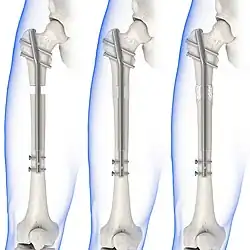

Internal fixators

Syndesmotic screws are the main, internal fixators used in surgeries for a Maisonneuve fracture. Two main types of syndesmotic screws are used: trans-syndesmotic screws (positioned at the level of the syndesmosis) and supra-syndesmotic screws (positioned above the syndesmosis).[14]

Based on several clinical results, syndesmotic screws are recommended to be fixed at least 1 centimetre proximal to the tibiofibular syndesmosis or 4 to 6 centimetres proximal to the tibiotalar joint line.[4][15] Cadaveric analyses, from a comparative study published in Foot & Ankle International in 1997, suggest that screw fixation at 2 centimetres proximal to the tibiotalar joint line is also adequate.[16] Biodegradable implants such as bioabsorbable screws, which do not require postoperative removal, may be used as an alternative to metallic hardware. However, biodegradable implants still limit rotation of the ankle and dorsiflexion of the foot.[4][6][13]